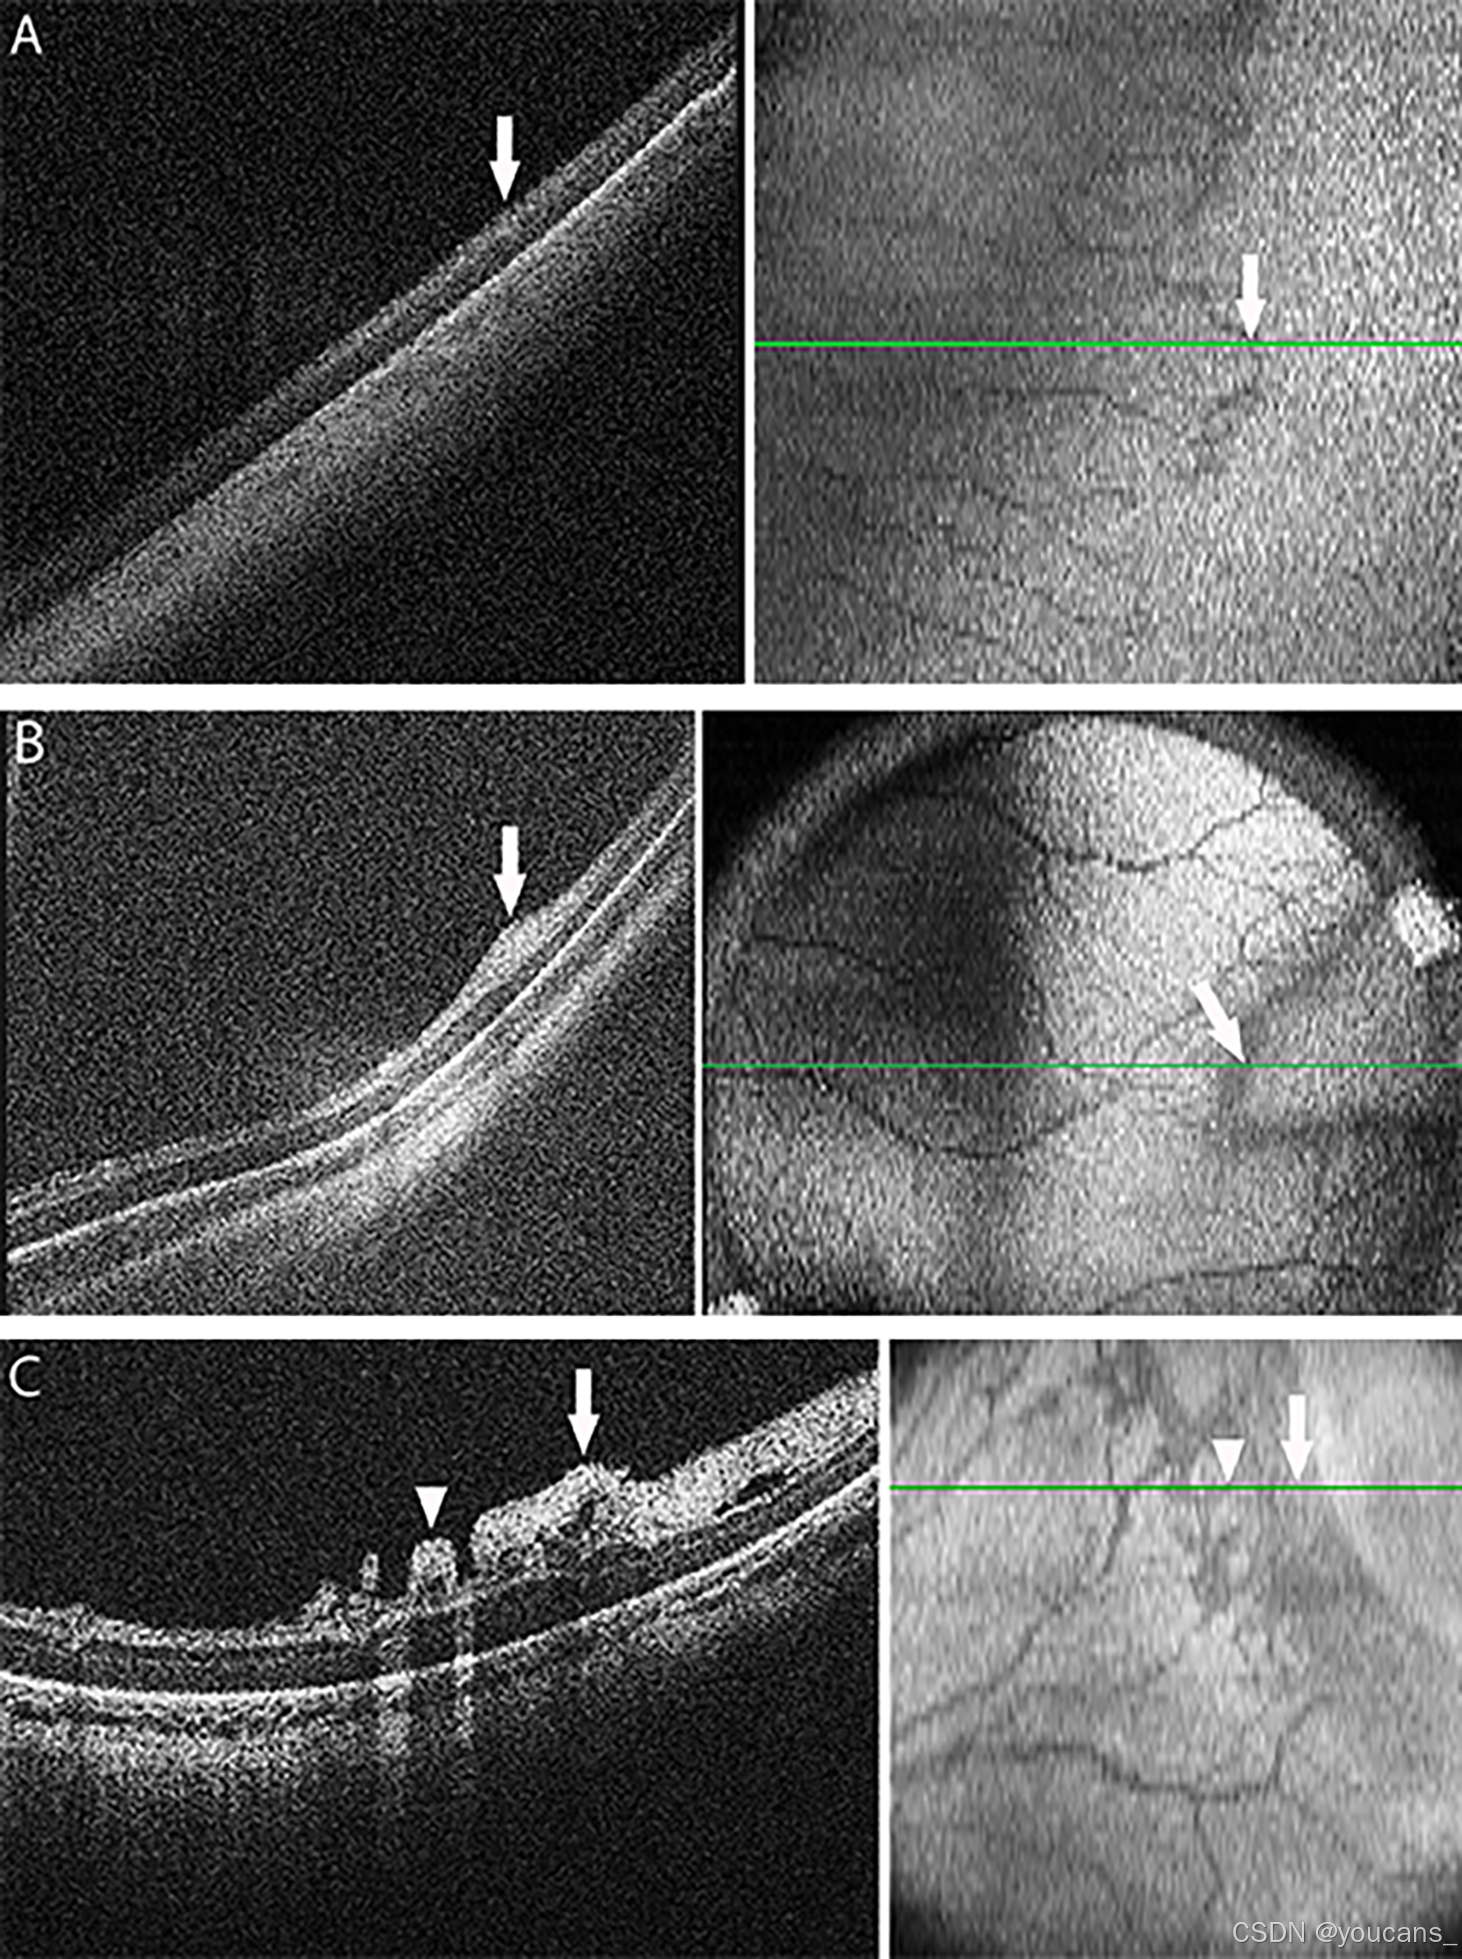

图6:光学相干断层扫描(OCT)图像展示了早产儿视网膜病(ROP)阶段1–3的例子。

OCT横截面B扫描图像(左侧)来自于构成OCT体积的光栅扫描,位置在绿色线的位置(右侧)。OCT面扫图像(右侧)是从OCT体积中汇总而来,视网膜血管中的血液在视网膜和脉络膜上方投下阴影。

(A) 阶段1界线(白色箭头)在横截面B扫描OCT图像(左侧)上与视网膜血管-无血管交界对齐(右侧,注意视网膜血管位于所有图像的左侧)。

(B) 阶段2脊(白色箭头)在横截面B扫描OCT图像(左侧)上,在视网膜内层局部增厚和膨出的位置,与面扫图像(右侧)上视网膜血管-无血管交界的较宽暗边缘对齐。

© 阶段3视网膜外新生血管增生,在横截面B扫描OCT图像(左侧)和面扫视图(右侧)上,分别位于(白色箭头)和交界后方(箭头)处。请注意,视网膜外血管中的血液也在视网膜和脉络膜上方投下阴影。